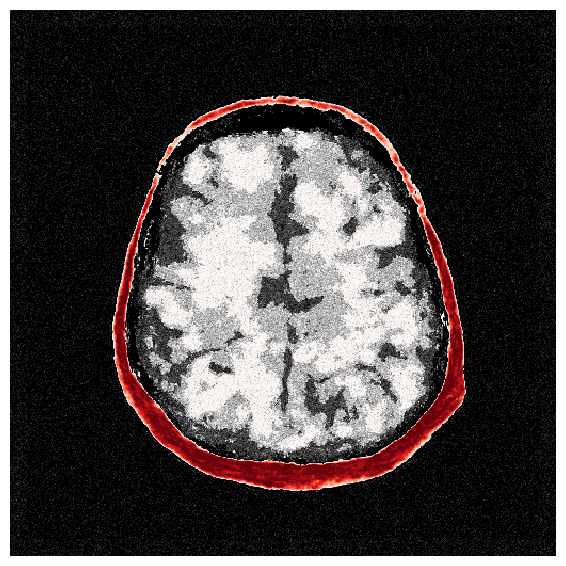

4.2.1 Brain prior samples:

The first step of implementing ASPIRE concerns obtaining samples from a realistic prior for the target parameter vector , in this case, gridded velocity parameters of human brains and skulls. The parameters collected in the MIDA dataset [56] correspond to a single 3D volume for the acoustic velocity collected from a single subject and will unfortunately not be appropriate to train a neural model that will generalize to other human patients. As far as we know, there is no dataset that includes acoustic velocity collected from many patients, so we made our own dataset based off the multi-subject FASTMRI dataset [57]. This custom dataset, detailed in Section \thechapter.A, comprises N=1000 diverse acoustic velocity parameters collected from different human patients, . This size of datasets facilitates generalization of the amortized posterior sampler across different datasets collected from unseen patients. The dataset is accessible via the repo ASPIRE.jl.

Appendix \thechapter.A FASTMRI acoustic dataset creation

Based off of the MRI dataset [57], we manually assigned acoustic values to MRI intensities by following the table of acoustic brain tissue properties in the supplemental section of [47]. Although MRI intensities are not necessarily related to acoustic tissue properties, we found that we could produce reasonably realistic acoustic parameters as compared to the acoustic parameters from the MIDA volume. In Figure 19, we show some example training acoustic parameters. We also plot the average and standard variation between all 1000 training samples in Figure 20. From these plots, we note that there are few similarities between training examples apart from the biologically consistent human brain structures.